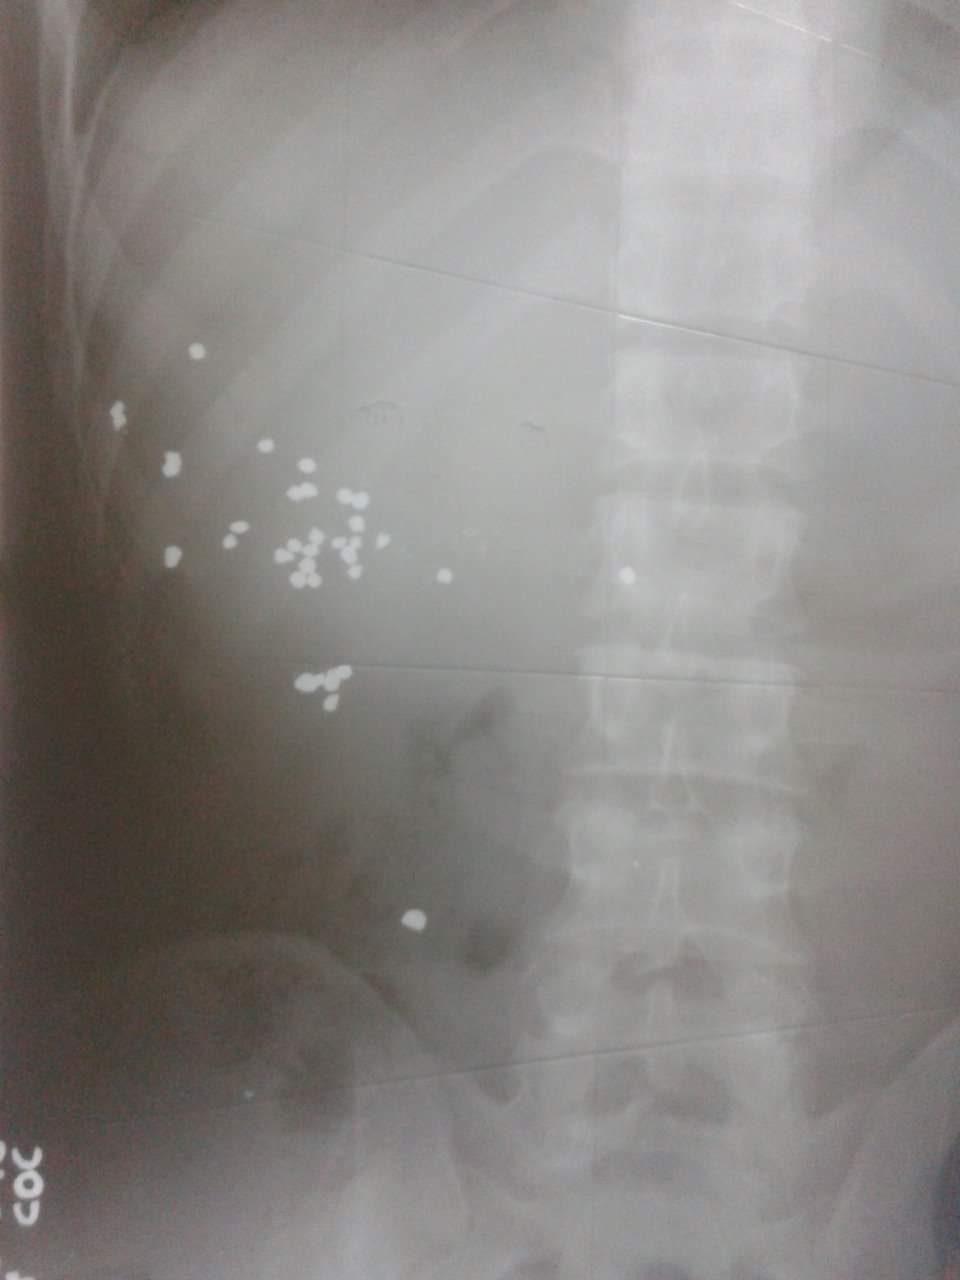

Sau khi chụp X-quang và CT, các bác sĩ phát hiện có nhiều dị vật, nghi là mảnh đạn hoa cải súng săn ở phần hạ sườn trái và đùi trái.

Hình ảnh những mảnh đạn được thấy trên phim chụp X-quang